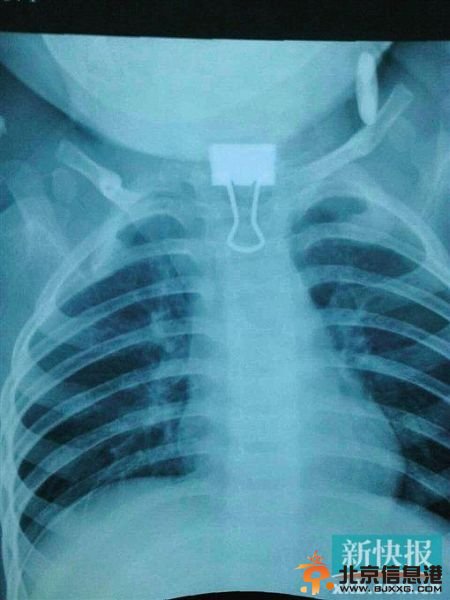

▲夹子卡在喉咙。 医生成功取出夹子。 医生曾经考虑切喉取物,手术能够成功也是险中取胜 一名1岁2个月的幼儿在玩耍时误将一只尖锐的夹子吞到了离食道口两公分的位置,情况

▲夹子卡在喉咙。 医生成功取出夹子。通讯员供图

昨日上午,小童(化名)的家属将女儿紧急送往深圳市儿童医院。小童在昨日上午9时至10时这段时间内,误将一个尖锐的物品夹吞入喉咙里面。据深圳市儿童医院耳鼻咽喉科主任梁振江介绍,小童来到医院后,经过拍片发现,进入她喉咙里面的夹子柄朝下,夹子心朝上,比较尖锐,“小孩子从卡住到拍片等,有活动,夹子往里面卡得深了一点点,小孩的食道入口不是成年人的宽度,卡在里面很难取出来”。